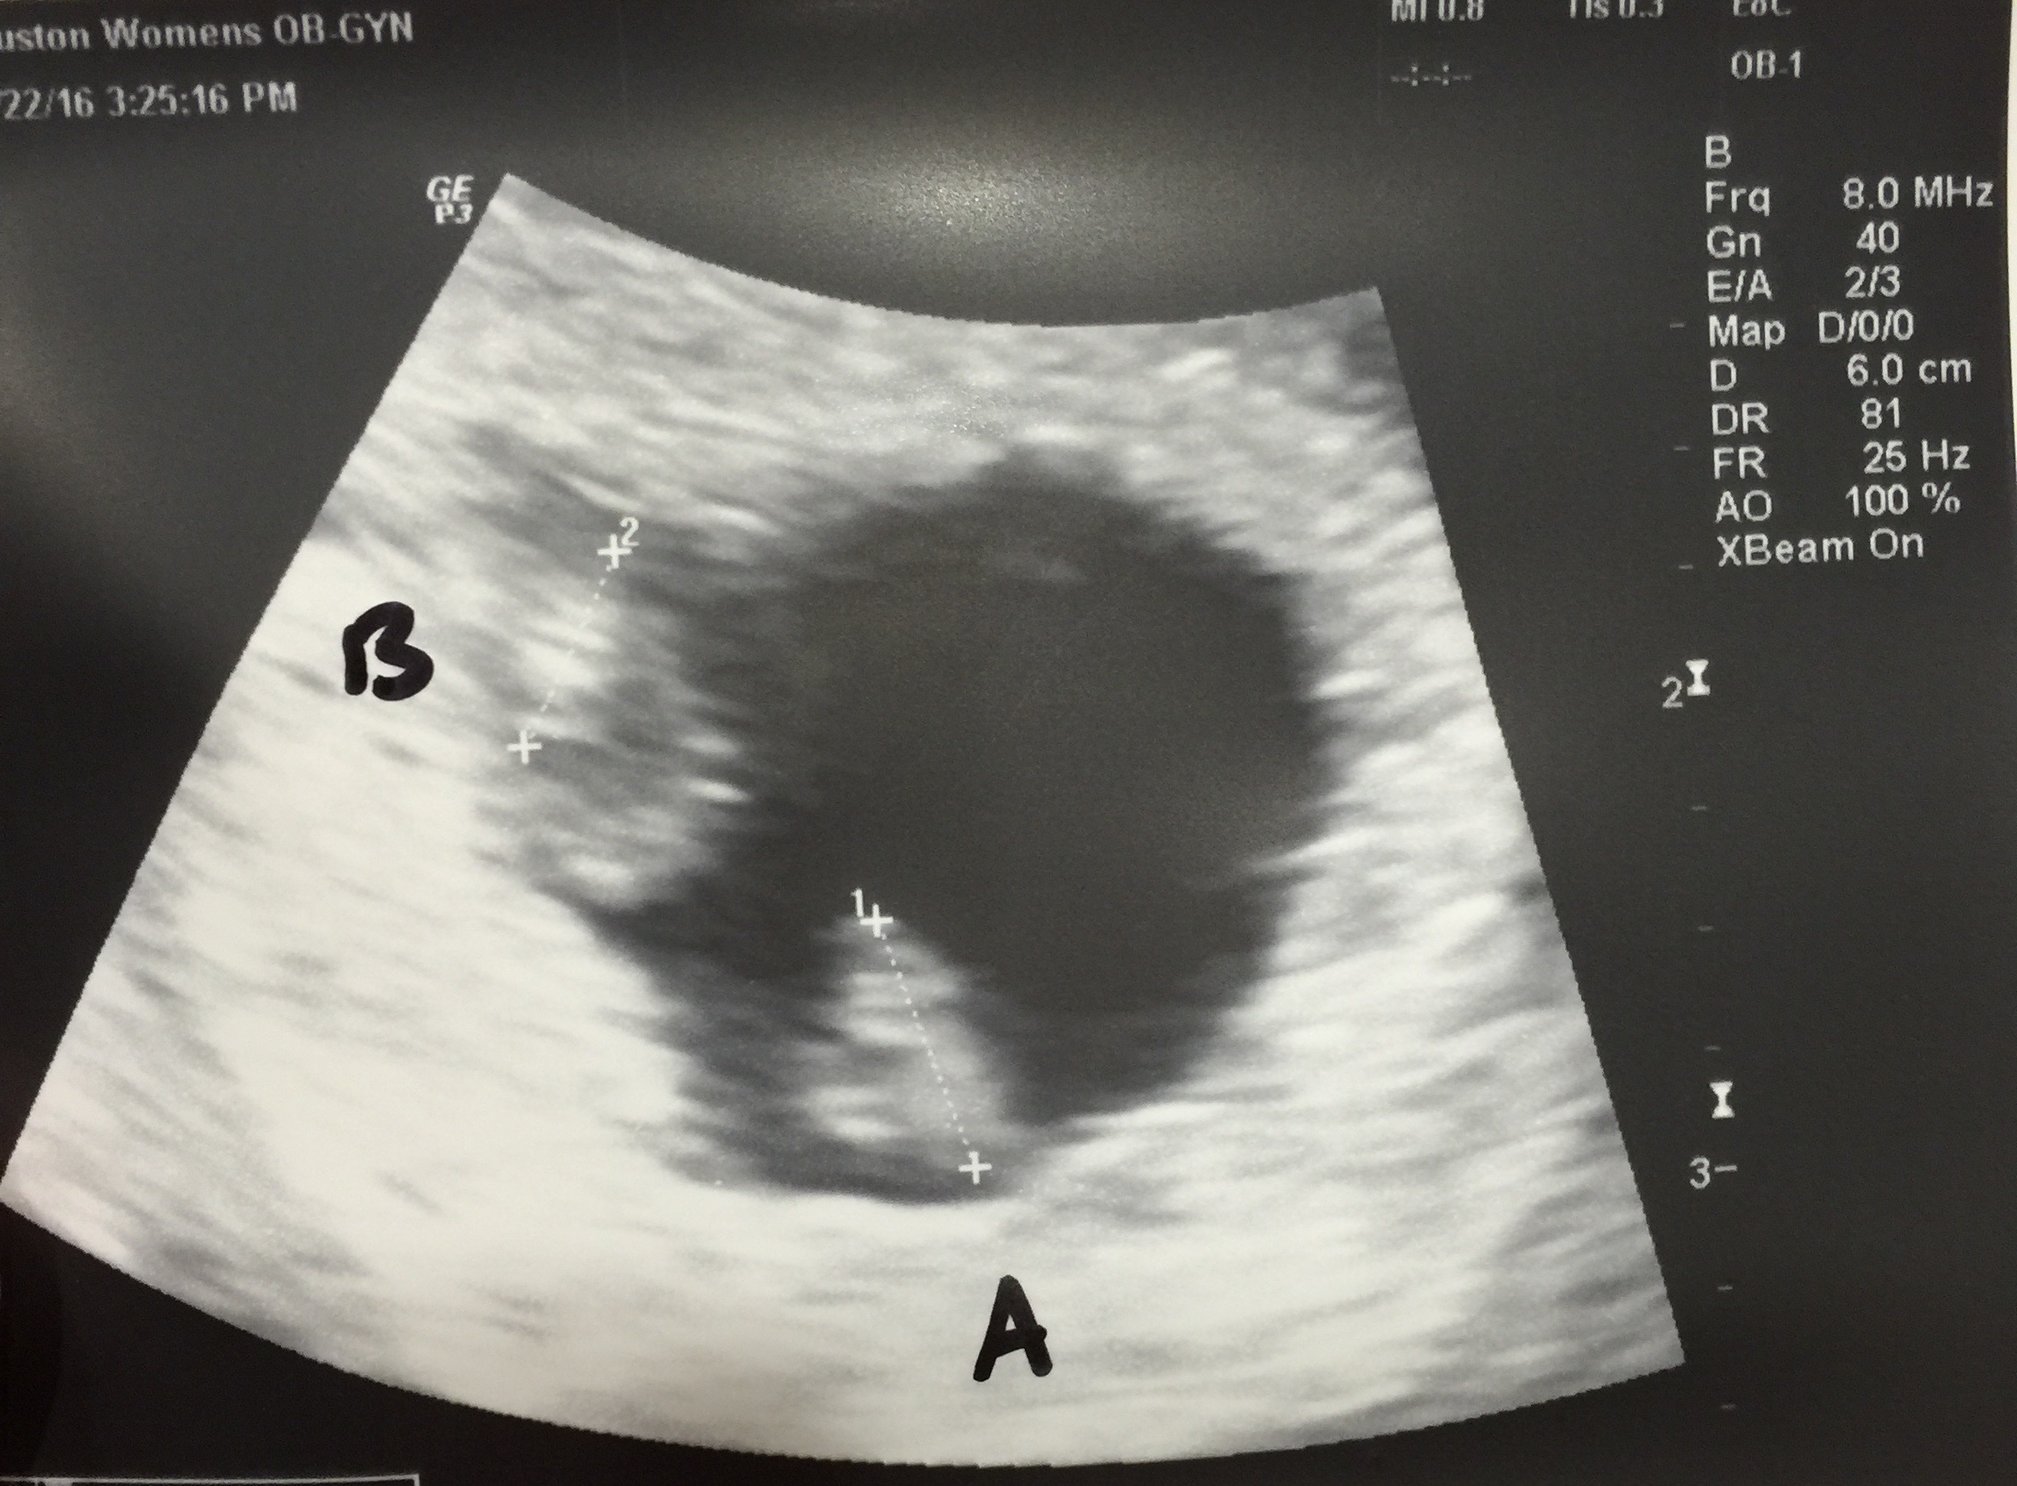

hi everyone! Thanks for all the best wishes! sooooo we heard the heart beats and...... 7 weeks exactly and we were beyond beyond beyond surprised when... She told us oh I see 2.... Wow I'm still in shock and *healthy and happy two little beans please* twins does not run in our families

little thing 2(B) is hiding a bit. So nervous y'all!!!! So surprised. Little miracles beans *healthy and happy*

7 weeks. She was zoomed in pretty tight to try to see a membrane. She's worried they are mono-mono since they are so close, but I know it's too early to see it